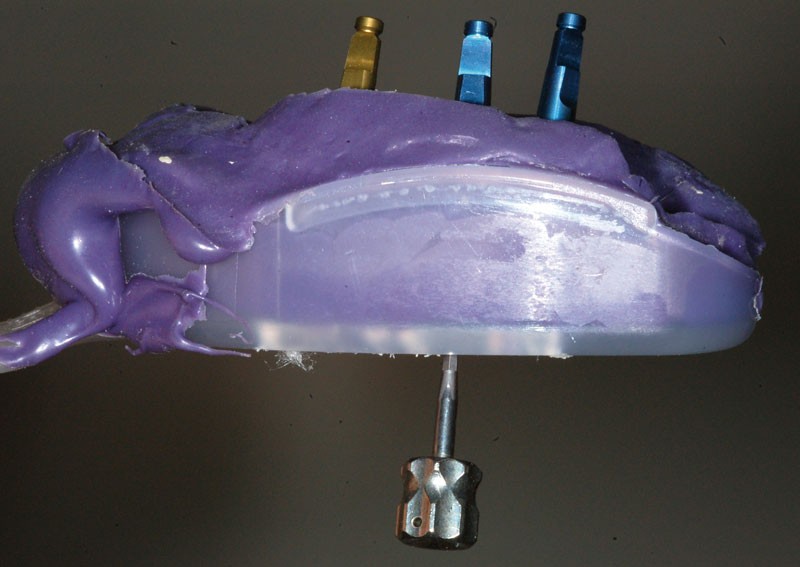

Une fois les transferts pick-up EV® transvissés, le porte-empreinte Tray, fenestré en regard des transferts, est chargé de matériau monophase Impregum™ Penta™ Soft (3M ESPE). Du matériau est déposé autour des transferts à l’aide d’une seringue. Après dévissage des transferts, ces derniers sont emportés dans l’empreinte et les analogues d’implants sont transvissés.

Une fois les transferts pick-up EV® transvissés, le porte-empreinte Tray, fenestré en regard des transferts, est chargé de matériau monophase Impregum™ Penta™ Soft (3M ESPE). Du matériau est déposé autour des transferts à l’aide d’une seringue. Après dévissage des transferts, ces derniers sont emportés dans l’empreinte et les analogues d’implants sont transvissés.

Une fois les transferts pick-up EV® transvissés, le porte-empreinte Tray, fenestré en regard des transferts, est chargé de matériau monophase Impregum™ Penta™ Soft (3M ESPE). Du matériau est déposé autour des transferts à l’aide d’une seringue. Après dévissage des transferts, ces derniers sont emportés dans l’empreinte et les analogues d’implants sont transvissés.

Une fois les transferts pick-up EV® transvissés, le porte-empreinte Tray, fenestré en regard des transferts, est chargé de matériau monophase Impregum™ Penta™ Soft (3M ESPE). Du matériau est déposé autour des transferts à l’aide d’une seringue. Après dévissage des transferts, ces derniers sont emportés dans l’empreinte et les analogues d’implants sont transvissés.

Une fois les transferts pick-up EV® transvissés, le porte-empreinte Tray, fenestré en regard des transferts, est chargé de matériau monophase Impregum™ Penta™ Soft (3M ESPE). Du matériau est déposé autour des transferts à l’aide d’une seringue. Après dévissage des transferts, ces derniers sont emportés dans l’empreinte et les analogues d’implants sont transvissés.